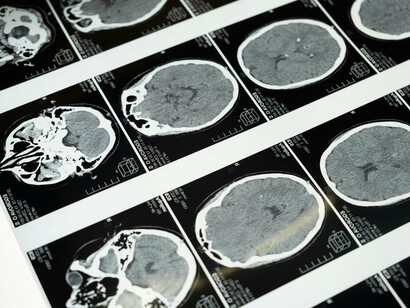

O diagnóstico correto entre tremor essencial e tremor parkinsoniano é crucial para o manejo adequado. Além da avaliação clínica detalhada, os neurologistas podem utilizar:

Testes de função neurológica.

Exames de neuroimagem, como ressonância magnética, para descartar outras causas.

Em alguns casos, exames de medicina nuclear, como SPECT ou PET, para avaliar a função dopaminérgica no cérebro.

Testes genéticos, especialmente em casos de início precoce ou forte história familiar.

É importante notar que, em alguns casos, o diagnóstico pode não ser imediatamente claro, e o acompanhamento ao longo do tempo pode ser necessário para estabelecer um diagnóstico definitivo.